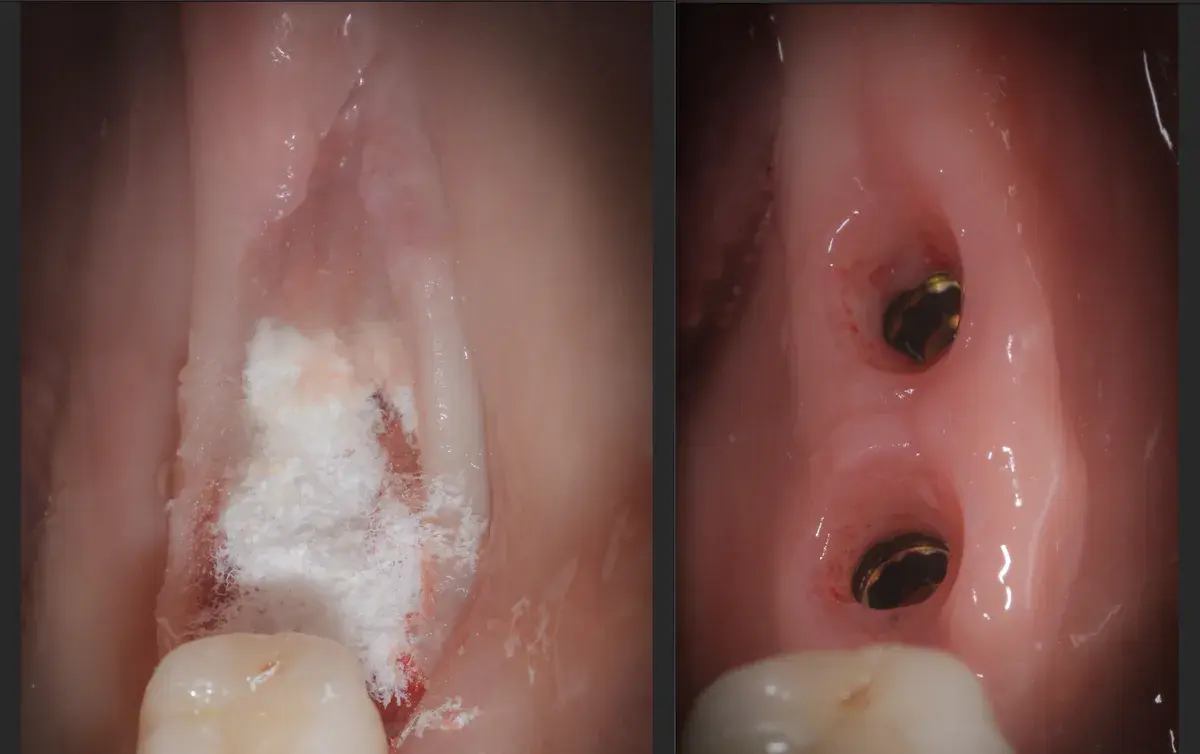

Cresta atrofica in zona 4.6 con difetto osteo-mucoso e cheratinizzata quasi assente: Bonebending 4.0 e impianto in unica seduta. Risultato a 3 mesi.

Caso clinico: espansione crestale ERE con impianto immediato e rigenerazione simultanea. Da ponte fallito a impianto in un'unica seduta.

Caso clinico di sinus lift crestale immediato post-estrattivo con innesto eterologo e colla di fibrina, espansori Kalodon. Follow-up CBCT a 2 mesi.